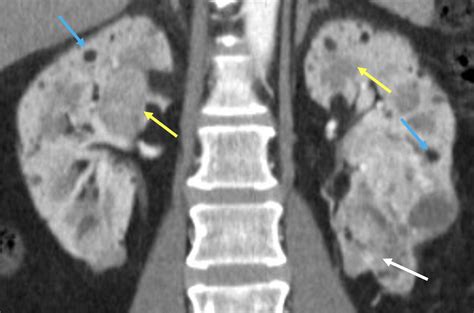

Renal Imaging and Surveillance

Renal involvement is a major contributor to morbidity in TSC, particularly in adults. The radiological surveillance of the kidneys is vital to prevent complications such as hemorrhage or renal failure. Imaging modalities of choice include ultrasound, CT scans, and MRIs.

The primary renal findings associated with Tuberous Sclerosis Radiology include:

• Angiomyolipomas (AMLs): These are the most common renal tumors in TSC. They are composed of blood vessels, smooth muscle, and fat. The presence of macroscopic fat is a diagnostic marker, which is best detected on MRI or CT scans using specific fat-suppression techniques.

• Renal Cysts: These can range from simple cysts to polycystic kidney disease, which, when occurring in TSC, often presents early in childhood and can lead to hypertension or decreased renal function.

• Renal Cell Carcinoma: While rare, the incidence is higher in TSC patients than in the general population, making it critical to distinguish between benign AMLs and potentially malignant masses.